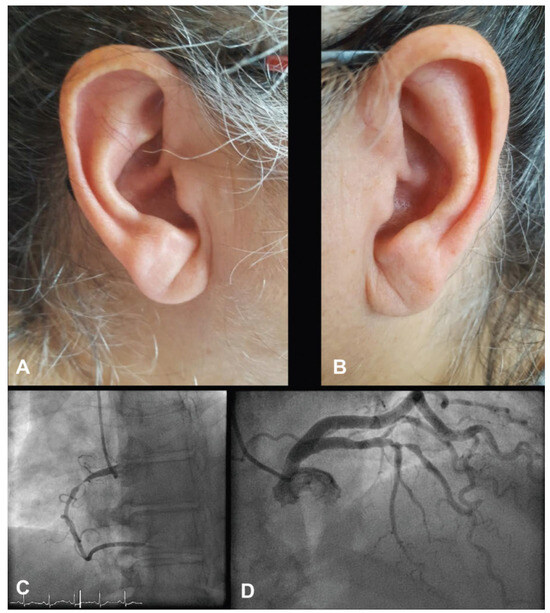

Interesting Images

Franck’s Sign

by Florian Rey, Ulysse Voirol and Georgios Giannakopoulos

Cardiovasc. Med. 2017, 20(6), 162; https://doi.org/10.4414/cvm.2017.00485 - 21 Jun 2017

Viewed by 206

Abstract

A 61-year-old obese female with Parkinson’s disease reported recurrent chest pain and exertional dyspnoea in the previous 24 hours [...] Full article

Show Figures

Figure 1